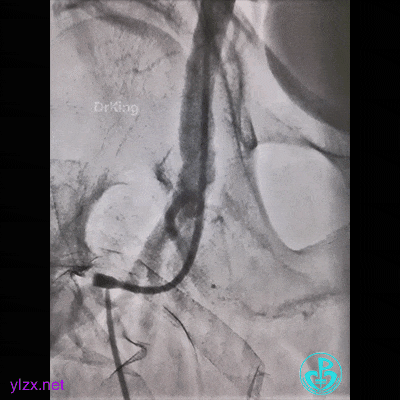

患者持续胸痛,先放这里,改入路开通心脏血管!

走左边,终于到位,造影。

左边EBU。

简单处理。

血运重建完成,胸痛缓解。生命体征平稳!